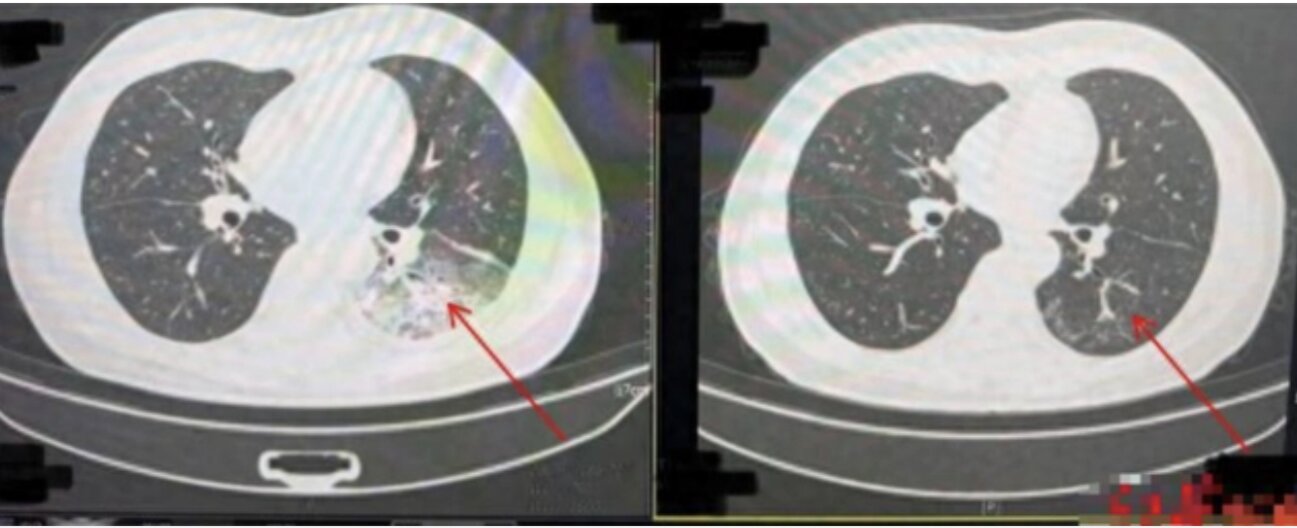

Kết quả chụp CT ngực cho thấy một nửa lá phổi trái của ông Lý trắng xóa. Kết quả nội soi rửa phế nang xác định ông Lý nhiễm vi khuẩn Legionella pneumophila gây viêm phổi.

Ảnh chụp CT trước khi điều trị cho thấy nửa lá phổi trái của ông Lý trắng xóa (bên trái) và ảnh chụp CT phổi sau khi điều trị khỏi (bên phải).